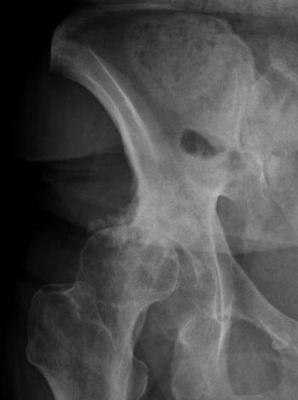

What's happening in your hip?

That groin pain needs to be evaluated; pull your knee to your chest, and then towards the opposite shoulder; is it painful in the hip? Our next newsletter covers this subject; it goes out tomorrow. You can sign up at the bottom of any page at Chiropractic Help.